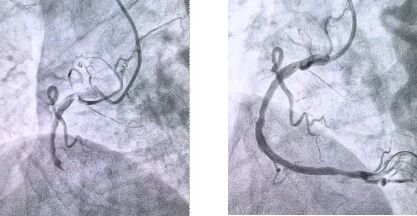

患者抵達醫(yī)院后,簡化掛號、繳費等中間環(huán)節(jié),迅速溝通病情,需要緊急介入治療,獲得家屬同意,立即送至導(dǎo)管室。造影顯示其右冠狀動脈中段完全閉塞,醫(yī)生迅速實施血栓抽吸,球囊擴張和藥物洗脫支架植入術(shù)。36 分鐘后,閉塞血管恢復(fù)正常血流,吳大爺?shù)难獕?、心率逐漸平穩(wěn),胸痛癥狀明顯緩解。術(shù)后三天,他便轉(zhuǎn)入普通病房進行康復(fù)訓(xùn)練,重拾健康生活。